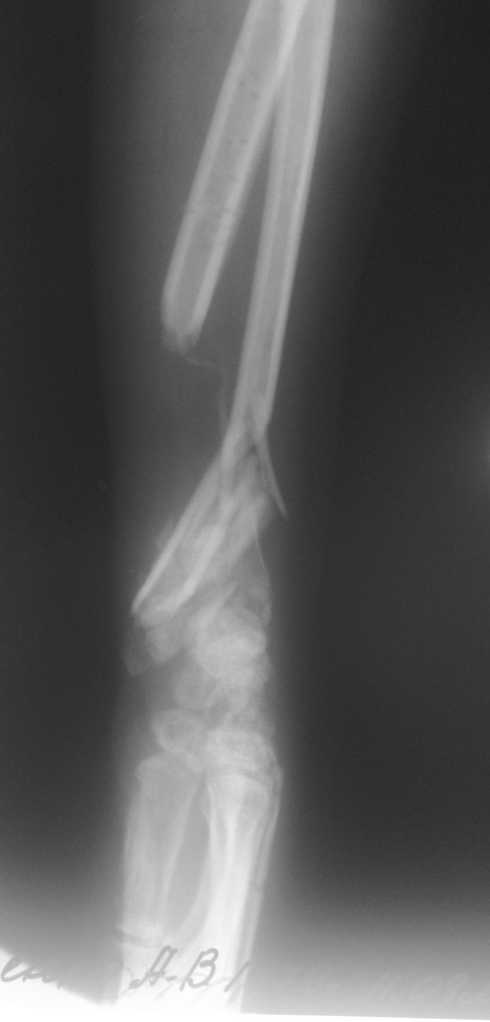

Больная Д. 30 лет плучила травму 12.07.09г, пассажир скутера -

тяжелая сочетанная травма брюшной полости и конечностей,

гемоперитониум, закрытый перелом н\3 ЛЕВОГО БЕДРА, открытый перелом

н/3 левого предплечья с дефектом обеих костей, рана голени.

С момента травмы перелом предплечья был фиксирован анкерно-спицевым

апаратом, проводилось лечение других сегментов.

В настоящий момент АВФ демонтирован, имеется следующая

рентгенологическая картина (см. приложение), имеется дефект обеих

костей и суставных поверхностей.

Имя     : бок проекция.jpg